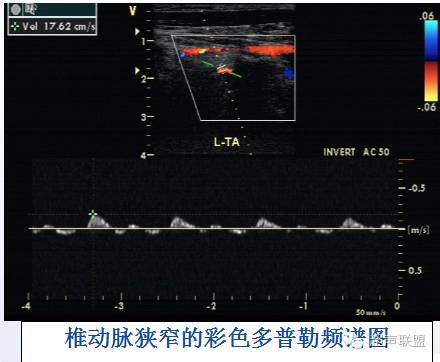

七、椎动脉闭塞性疾病

* 声像图表现:

2、CDFI及PW:CDFI见椎动脉管腔局限性狭窄,狭窄处血流增速,狭窄即后段有湍流。

健侧椎动脉血流量增加,血流加速。